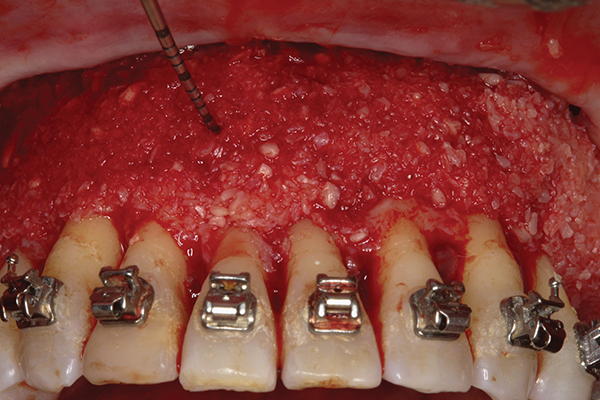

Fig 12. Particulate bone grafting performed to augment deficient dentoalveolar bone (mineralized corticocancellous freeze-dried

bone allograft); 4 mm of bone augmentation thickness demonstrated.

Figure 12